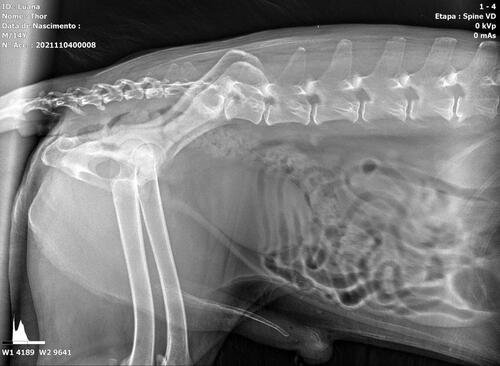

Thor é um senhorzinho que sofre com a síndrome da cauda equina, que é uma doença grave causada pela compressão e inflamação do feixe de nervos na parte inferior do canal vertebral. A gravidade se dá ao fato de poder resultar em paralisia, incontinência intestinal / urinária e a outros problemas de sensibilidade e perda de movimento.

Thor já apresenta todos os sintomas e precisa passar por procedimentos veterinários, necessita de fisioterapia para estimular o retorno do controle esfincteriano (válvula urinária e fecal) e medicações. Uma cirurgia também pode ser o caminho de acordo com o neurologista veterinário.